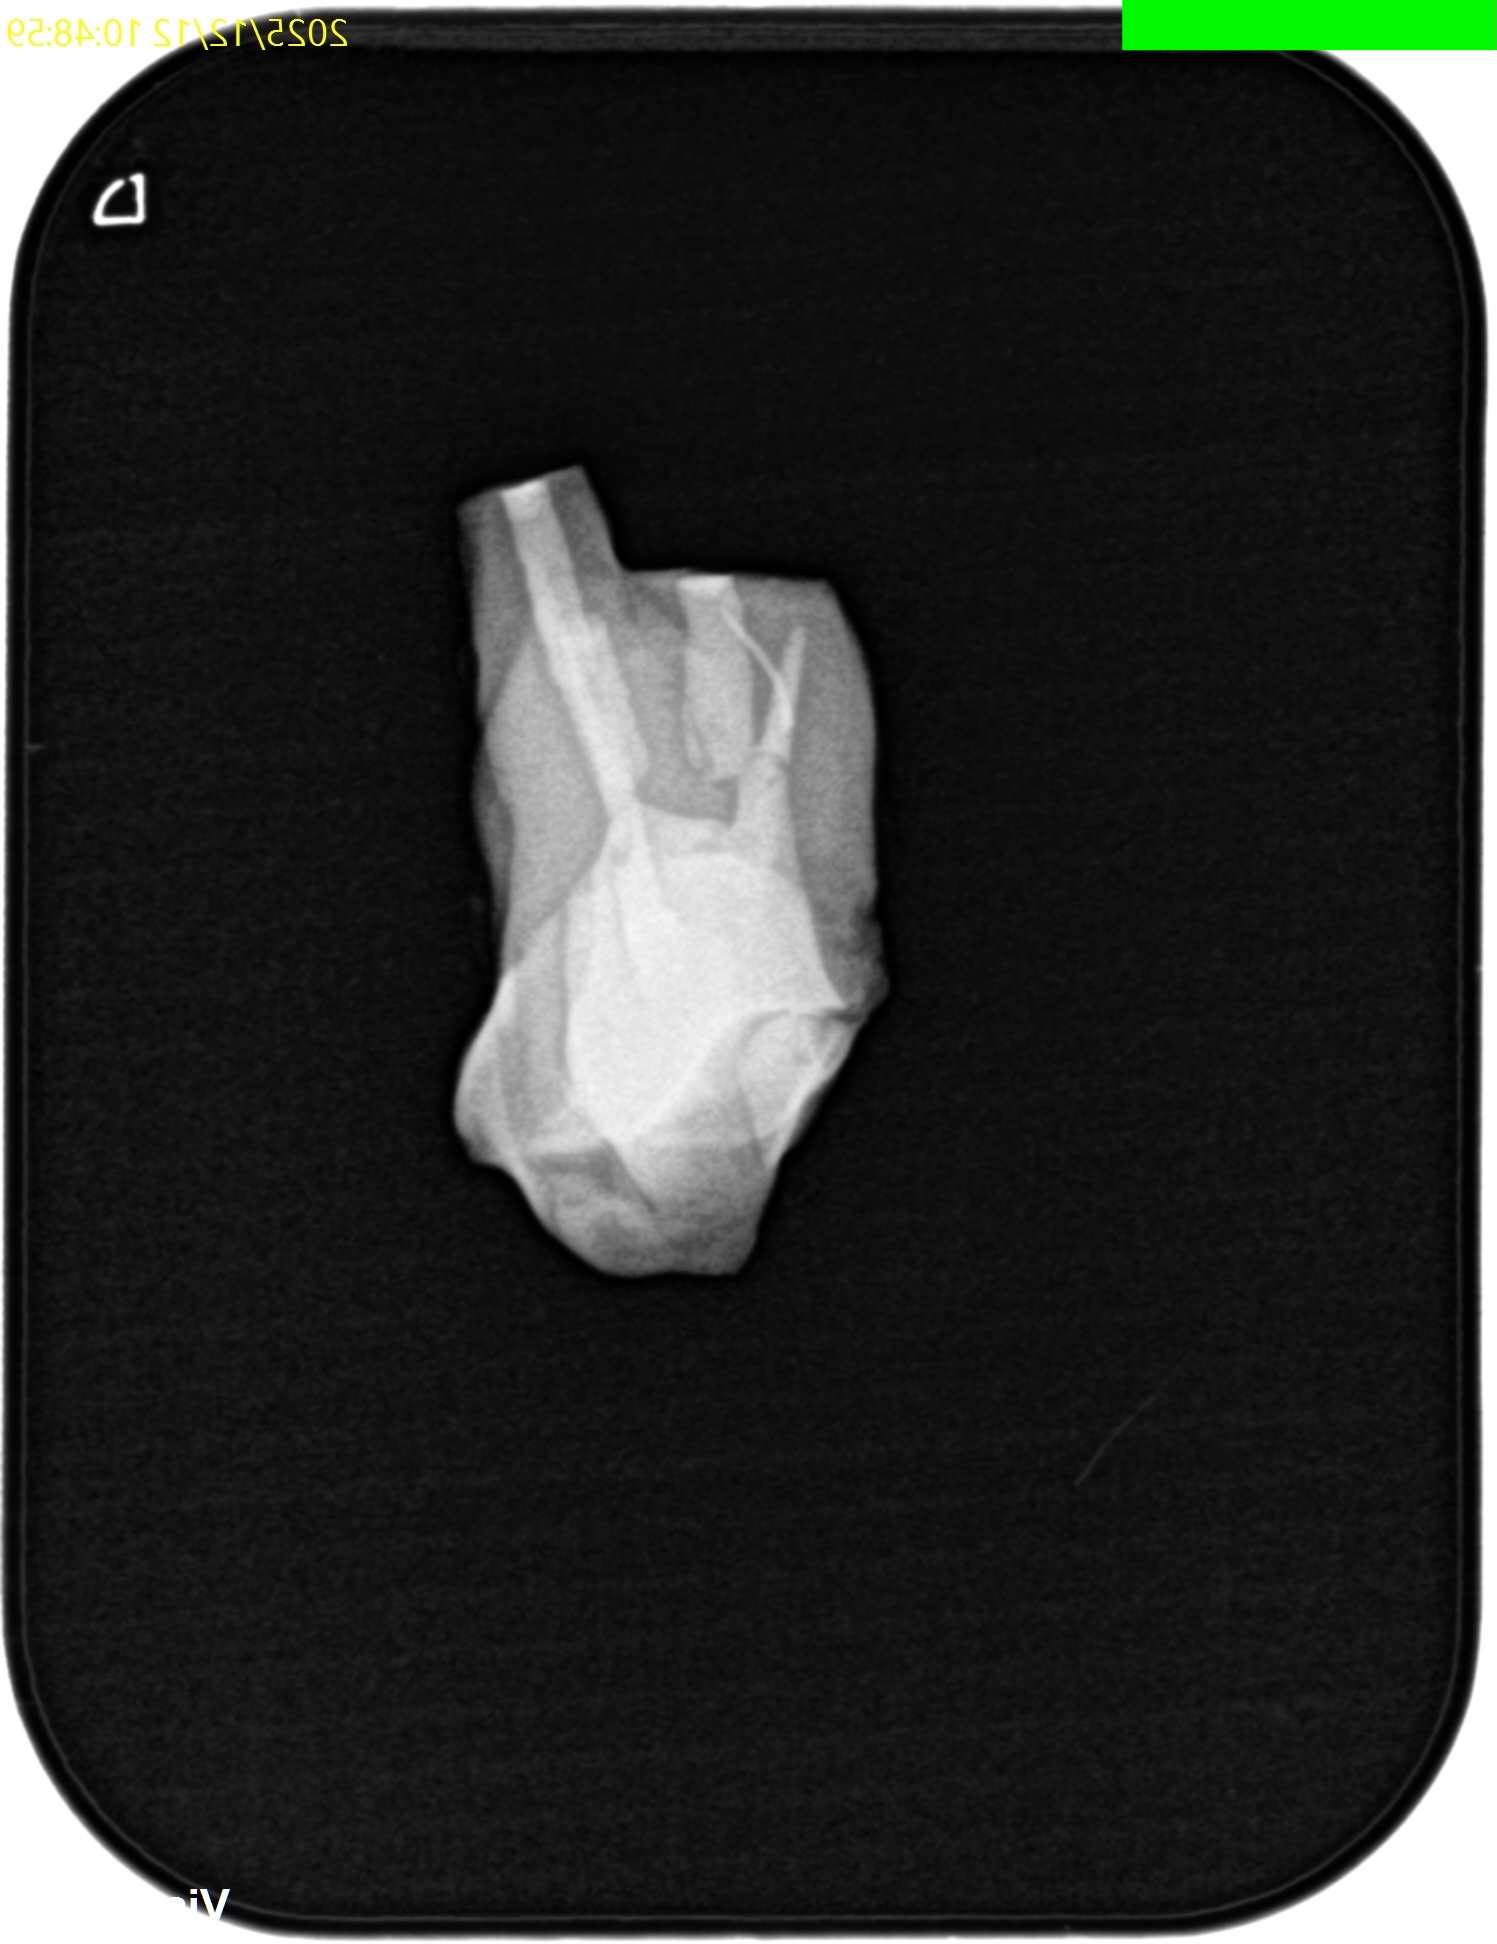

メチレンブルーで染め出してRoot resectionした。

切断部分をメチレンブルーで染め出した後に逆根管形成した。

ファイルが破折しているMBから折れたファイルを取り出そうとするが困難であった。

仕方がないのでそのままにして逆根管形成を進めていった。

逆根管充填した。

術後にPAを撮影した。

折れたファイルはIntentional Replantationの術式では取れなかった。

が、それをあえて取ろうという考えは私にはない。